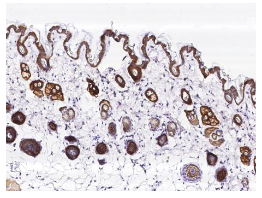

1【免疫组化】

检测TROP2在肿瘤和正常组织中的表达,信噪比高